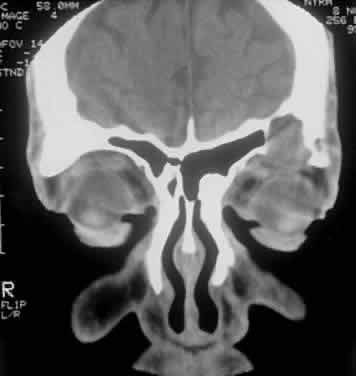

Computed tomography (CT) accurately demonstrates the molding of the mass to orbital structures, such as the globe and orbital bones, without bony erosion except in large cell lymphoma (Fig. 7). CT is used to localize the lesion, which tends to be unilateral and in both the intraconal and extraconal spaces. Lesions limited to the conjunctiva tend to be more benign with a better long-term prognosis, whereas those that extend into the orbit tend to be more malignant. Conjunctival lesions remain localized in 90% of cases, whereas orbital and lid lesions have a higher rate of systemic extranodal involvement.63 Lymphoid lesions of the lacrimal gland appear as a diffuse vertical expansion of the gland, which mold to both the globe and orbital bone without producing a bony fossa or erosion64 (Fig. 8). If the lesion extends beyond the orbital rim, the palpebral lobe of the gland is involved, and posterior or orbital lobe involvement appears as a straight line against orbital fat. Pleomorphic adenoma, on the other hand, appears as an oval, globular lesion with, in 80% of cases, adjacent bone changes caused by the firmer stroma of the tumor. Because epithelial tumors usually arise in the orbital lobe, extension beyond the orbital rim is not a feature.65 CT scan cannot distinguish between inflammatory and lymphoid lesions, because both lesions are homogeneous and enhance with intravenous contrast, and at biopsy, orbital lymphoid lesions are pink with a friable texture caused by the absence of stroma.66–68 The subtype and malignancy of the lesion can only be determined morphologically. The following subtypes of B-cell nonHodgkin's malignant lymphoma—extranodal B-cell marginal zone lymphoma, follicle center cell lymphoma, small lymphocytic lymphoma, lymphoplasmacytoid lymphoma, mantle cell lymphoma, large cell lymphoma, and Burkitt's lymphoma—are discussed in the approximate order of frequency with which they occur in the orbit.

Fig. 8. A CT scan, axial view, of a B-cell lymphoma localized to the anterior orbit bilaterally, with left lacrimal gland involvement and a normal adjacent lateral wall.